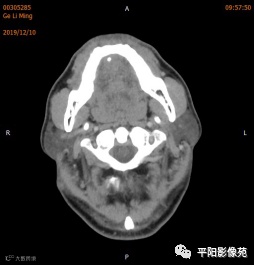

双侧颌下腺、腮腺对称,形态完整,右侧颌下腺强化程度较左侧略低,其内涎腺管增粗,周围脂肪间隙清晰,邻近骨质未见异常,右侧涎腺走行区可见结节样致密影,较大者大小约0.5cm,双侧颌下软组织对称,未见异常密度,所扫范围颈部未见明显肿大淋巴结。

考虑右侧涎腺管结石。

右侧颌下腺强化程度较左侧略低,涎腺管扩张,考虑炎性改变,请结合临床。